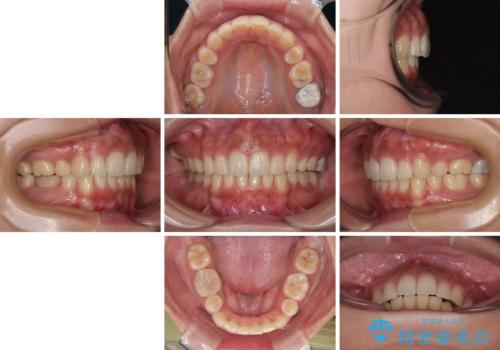

口元の突出感が改善されてことで、下唇に引っかかっていた上顎前歯も気にならなくなりました。